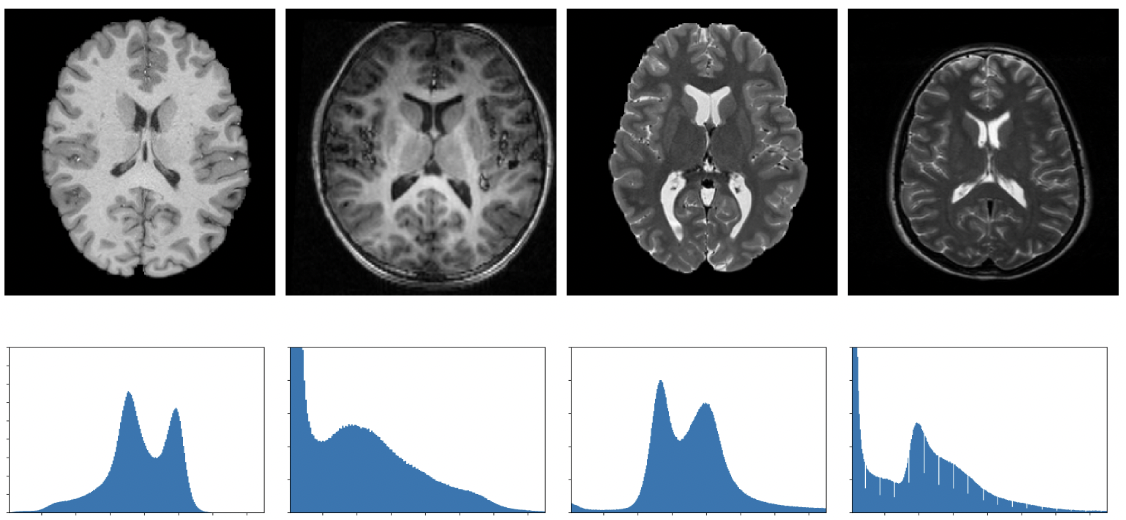

A Lifelong Learning Approach to Brain MR Segmentation Across Scanners and Protocols

Neerav Karani, Krishna Chaitanya, Christian F. Baumgartner, Ender Konukoglu

Lecture Notes in Computer Science, 476-484 (2018)

journal URL

preprint URL